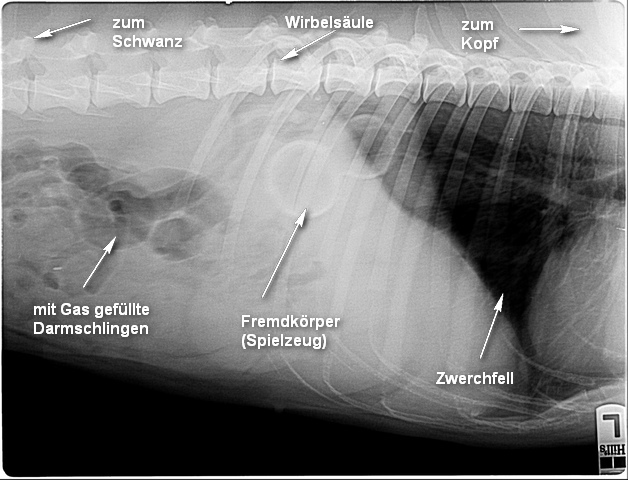

wieder Dienst und entschied kurzerhand eine Röntgenaufnahme des Bauchbereichs zu machen. Die

anschließende Mitteilung ließ mich nicht gerade Freudensprünge

vollziehen. Die Diagnose lautete, Gina hat ein Spielzeug im Magen -

oder auch alles nur geklaut wie sich später herausstellen sollte. Bedenklich

war allerdings, dass Gina trotzdem minimal Kot- und Harnabsatz hatte.

Da der Verdacht nahe lag, dass sich dort noch etwas versteckte, führte

Frau Doktor Leppelt eine Sono und einen weiteren Tastbefund durch - ja

da war doch noch etwas.

Eine

von diesen beiden Kong-Kullern hatte sich schon in einer Darmschlinge

versteckt und die Öffnung in ihr sorgte für den noch minimalen Kot- und

Harnabsatz.

Hier wurde der Übeltäter - Kullerkong - nach einem weiteren eingehenden Tastbefund dingfest gemacht.